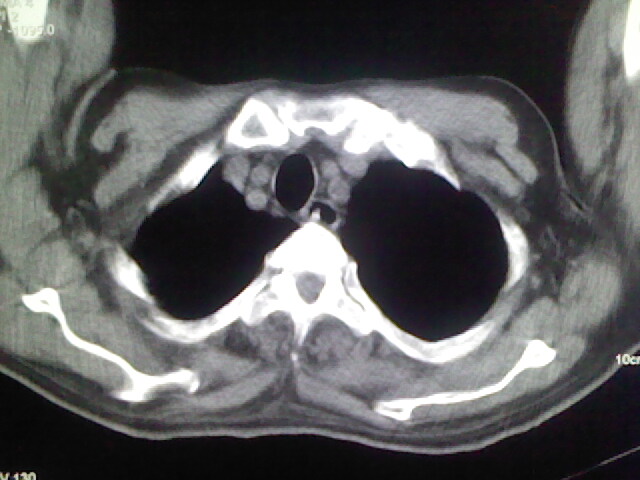

男,70岁,脑出血,长期卧床,左侧背部可触及肿块

慢性间质性炎症,与老年患者长期卧床相关,胸壁软组织及肋骨未见异常。

背部没见到肿块呀,有感染灶。

肺部感染,背部筋膜增厚,考虑坠积性水肿或炎症